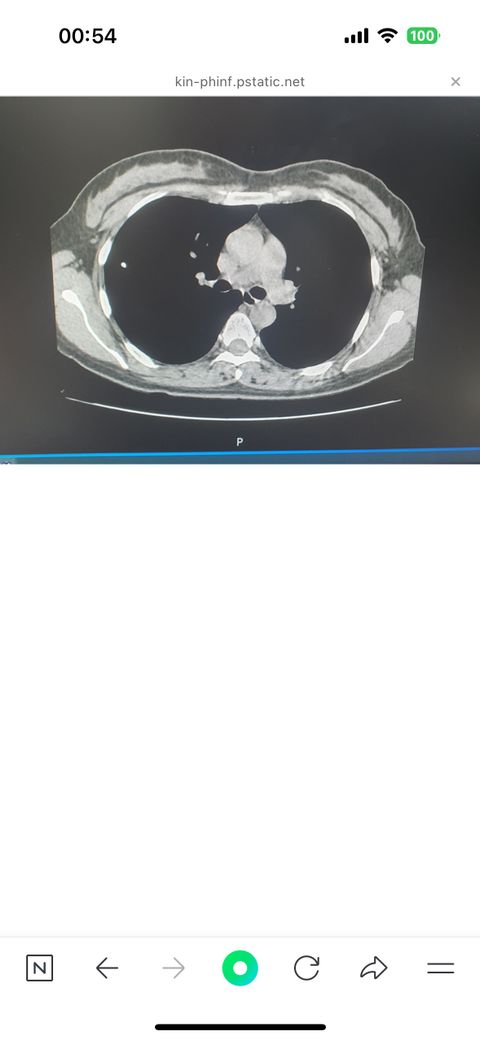

석회성 폐결절이 사진과같은 건가요??

5mm정도의 폐결절이 하나있는데

사진처럼 검은 폐사진바탕에 하얀점

하나가있는데

이런경우는 석회성결절이라고한거같은데

맞나요??

아니면 석회성결절은 어떻게 판단하는거예요?

• 1번 째 사진

CT에서 조영제가 들어가지 않은 부위인데 하얗게 보이면 칼슘 성분이 있는 것으로 생각합니다. 같은 폐결절이어도 칼슘으로만 되어 있는 경우에는 크게 걱정하지 않아도 됩니다. 흉터의 일종으로 생각합니다.

폐결절의 판독에 대해 궁금하시군요. 석회성 결절의 경우 엑스레이나 흉부 CT와 같은 방사선 검사에서 뼈와 비슷한, 혹은 더 밝은 음영을 보입니다. 조영제와 관계 없이 음영이 높아서 비조영 영상에서도 하얗게 관찰되는 편입니다. 이러한 영상적 특징을 보고서 석회성 결절이라는 의심을 할 수 있는 것입니다. 물론 함께 촬영된 영역과 환자의 증상 모두 함께 판단해야하는 문제이므로 진료받으시는 의사에게 정확한 설명을 들어보시기 바랍니다.

맞습니다. CT영상의 경우 조영제를 사용하지 않은 영상에서

뼈와 같은 정도의 하얀색을 보이는 경우 "석회화"라고 이야기합니다.

석회화된 결절은 CT 스캔에서 고밀도의 하얀 점으로 나타납니다. 제시하신 사진은 석회성 육아종, 석회성 결절의 가능성이 있어 보입니다.